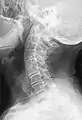

Block vertebrae

Block vertebrae occur when there is improper segmentation of the vertebrae, leading to parts of or the entire vertebrae being fused. The adjacent vertebrae fuse through their intervertebral discs and also through other intervertebral joints so that it can lead to blocking or stretching of the exiting nerve roots from that segment. It may lead to certain neurological problems depending on the severity of the block. It can increase stress on the inferior and the superior intervertebral joints. It can lead to an abnormal angle in the spine, there are certain syndromes associated with block vertebrae; for example, Klippel–Feil syndrome. The sacrum is a normal block vertebra.